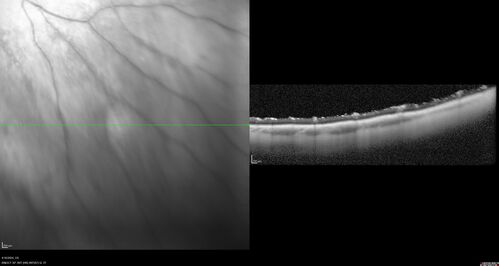

Posterior Pigment Dispersion Syndrome

81 year old man with cataract surgery 30 years ago and normal vision who had bilateral vitrectomy for dense floaters and has pigment on his IOL surface and all over the retina (but not on the cornea) VA 20/25 OU